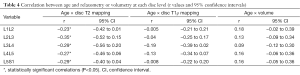

As shown in Table 4, we observed a negative linear correlation between T2 relaxation times and age at all lumbar disc levels (P<0.02 at all levels). There was no correlation between age and volumetry for any disc (P>0.07 at all levels). We also observed no relationship between age and T1ρ values for any disc level (P>0.06 at all levels). BMI, height and weight were not correlated with any lumbar IVD relaxometry measurement.

The stratification of the IVD into NP, AAF and AAF made possible to analyze separately the correlation of each sub-region with ageing (Figure 6). Table 2 shows the correlation values (r) for each disc sub-region (NP, and PAF AAF) at each disc level (L1L2 to L5S1). T2 relaxation times of NP and PAF correlate negatively with aging at all disc levels, except for the sub-region PAF in L5S1 disc. T1ρ relaxometry correlates only with the sub-region NP of L1L2 and L3L4 IVDs.